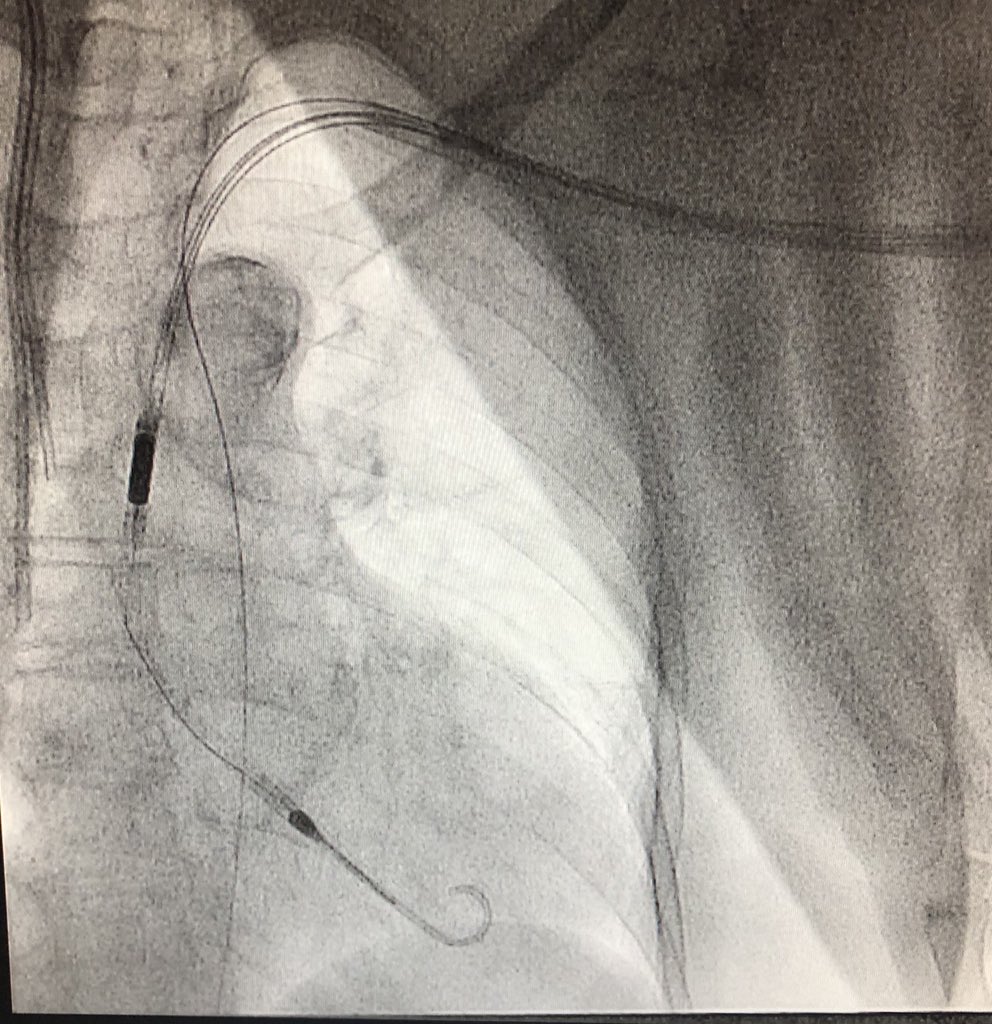

After considering making an early transition to industry but struggling to walk away from the lab, damn it feels good to get the #CHIP train rolling again! 1st #PercAx LM #rotapro in NJ & single #safefemoral access with 7fr dest via CP. Off-label but 💯! Props to @jason_wollmuth

RajTayalMD's tweet image. After considering making an early transition to industry but struggling to walk away from the lab, damn it feels good to get the #CHIP train rolling again! 1st #PercAx LM #rotapro in NJ & single #safefemoral access with 7fr dest via CP. Off-label but 💯! Props to @jason_wollmuth